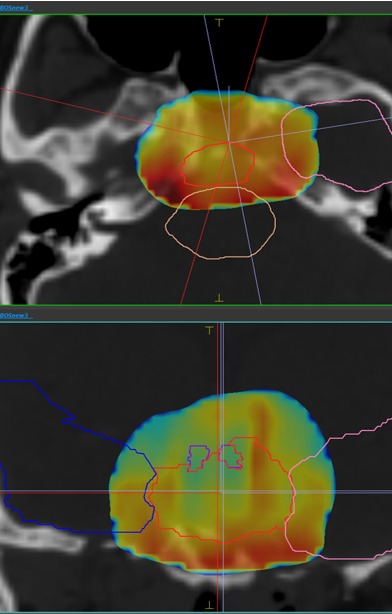

The comparative planning workshop featured an extremely complex case. The four participating centres each created comparative proton-photon treatment plans. The CTV was abutting critical organs at risk such as optic chiasm, optic nerves, brainstem and hippocampi. In addition to this, the requirement for a high prescription dose meant that significant optimization trade-offs were required.

The Australian Bragg Centre team utilized MonacoPT to generate the proton therapy treatment plan and used unique features including constrained optimization, dynamic spot placements and Linear Energy Transfer (LET) analysis. The robustness optimization display also allowed the team to view approximate doses during optimization, not having to navigate through multiple windows.

Dose view

LET view